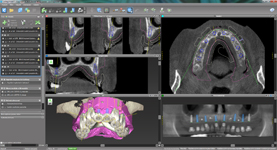

coDiagnostiX – Dental Wings

Jedná se o externí plánovací program, spojený se zubní laboratoří a frézovacím centrem, který využívá dat získaných z 3D rentgenu čelisti, otisku zubů a dásně (scanu zubů a dásně) a finálního návrhu protetické náhrady.

Tento program umožňuje tříprostorovou počítačovou simulaci při plánování pozic implantátů. Součástí programu je i databáze, ve které mohou být uloženy všechny typy implantátů od všech výrobců, včetně jejich délek, průměrů i tvarů.

Lékař si vytvoří všechny typy zobrazení potřebných pro naplánování – tedy 2D snímky (panoramatický), příčné řezy i 3D model.

Vidí zde i důležité anatomické útvary – čelistní dutinu, průběh nervu atd. Po proměření množství kosti – šířky i výšky vybere z databáze vhodný typ implantátu a umístí ho do požadované lokality. Ihned vidí jeho pozici ve všech 3 rovinách a na

všech snímcích i 3D modelu. Může upravovat podle potřeby jeho pozici, sklon atd.

Všechny vybrané a správně umístěné simulované implantáty se ukládají do „počítačové karty“ pacienta s jejich pozicí, délkou, průměrem, typem i sklonem. V programu také lékař navrhuje chirurgické šablony pro řízenou nebo navigovanou implantaci.

Lékař i pacient tedy ještě před vlastní operací vidí, jak by mělo ošetření probíhat a vypadat.